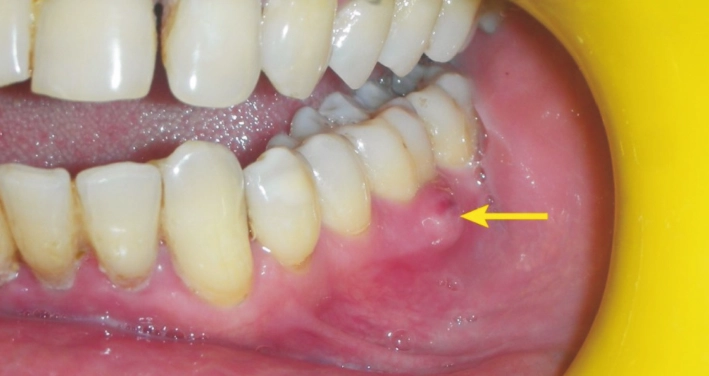

Then come the other guests to this unpleasant party. You might notice sudden sensitivity to hot and cold temperatures that lingers long after the source is gone. Your gums around the tooth may become red, swollen, and shiny. In some cases, the swelling can be significant, causing your face to look puffy on one side. You might even be able to see or feel a pimple-like bump on your gums near the root of the tooth – that's a draining fistula, and it's a classic sign of a tooth abscess trying to release pressure.